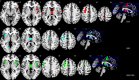

Corticobasal degeneration is a scarce neurodegenerative disease, which can only be confirmed by histopathological examination. Reported to be associated with various clinical syndromes, its classical clinical phenotype is corticobasal syndrome. Due to the rareness of corticobasal syndrome/corticobasal degeneration and low numbers of patients included in single studies, meta-analyses are particularly suited to disentangle features of the clinical syndrome and histopathology. Using PubMed, we identified 11 magnetic resonance imaging studies measuring atrophy in 22 independent cohorts with 200 patients contrasted to 318 healthy controls. The anatomic likelihood estimation method was applied to reveal affected brain regions across studies. Corticobasal syndrome was related to gray matter loss in the basal ganglia/thalamus, frontal, parietal, and temporal lobes. In corticobasal degeneration patients, atrophy in the thalamus, frontal, temporal, and occipital lobes were found. Finally, in a conjunction analysis, the bilateral thalamus, the bilateral posterior frontomedian cortex, posterior midcingulate cortex and premotor area/supplementary motor area, and the left posterior superior and middle frontal gyrus/precentral gyrus were identified as areas associated with both, corticobasal syndrome and corticobasal degeneration. Remarkably, atrophy in the premotor area/supplementary motor area and posterior midcingulate/frontomedian cortex seems to be specific for corticobasal syndrome/corticobasal degeneration, whereas atrophy in the thalamus and the left posterior superior and middle frontal gyrus/precentral gyrus are also associated with other neurodegenerative diseases according to anatomic likelihood estimation method meta-analyses. Our study creates a new conceptual framework to understand, and distinguish between clinical features (corticobasal syndrome) and histopathological findings (corticobasal degeneration) by powerful data-driven meta-analytic approaches. Furthermore, it proposes regional-specific atrophy as an imaging biomarker for diagnosis of corticobasal syndrome/corticobasal degeneration ante-mortem.